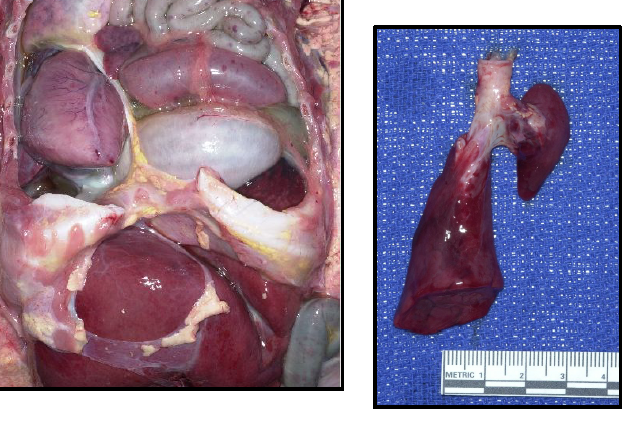

Letulle method almost always - important to preserve anatomic relationships

necrotizing enterocolitis (NEC) totalis

inflammation/infection of bowel causing tissue death, perforation, sepsis; commonly affects premature infants.